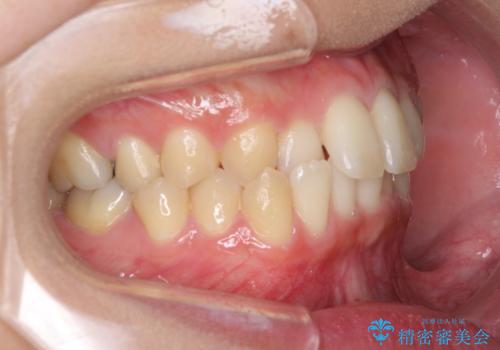

- 前歯のクロスバイトを気にして来院され患者様です。

定期的に日本には帰国するものの、日ごろは海外でお仕事をされているとのことで、インビザラインによる治療を希望されました。

トラブルが起こった時に対応ができない、来院を帰国のタイミングに合わせなければならないため治療が長期化するなど困難はありますが、ワイヤー矯正と比べると治療を進めやすいといったメリットがあるので、インビザラインにて矯正治療を行うこととしました。